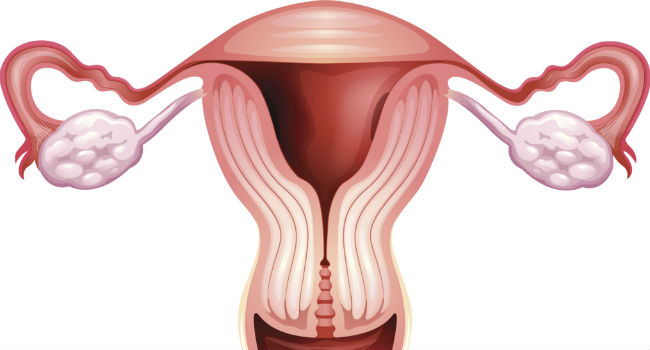

Recentemente a pílula anticoncepcional passou a ser associada a casos de trombose, AVC e infarto. Fato é que os hormônios externos mexem com o corpo inteiro e oferece outros riscos além desses. A Organização Mundial da Saúde elaborou um documento que indica em que casos a pílula anticoncepcional combinada, que leva hormônios estrógeno e progestágeno, oferece mais riscos que benefícios e deve ser evitada.

Pílula anticoncepcional: quais são os riscos

Mulheres com sangramento vaginal inexplicado

Pode haver uma causa, ainda oculta, que impeça o uso da pílula. Vá ao médico e, uma vez descoberta a doença, será decidido se o anticoncepcional continua ou não.